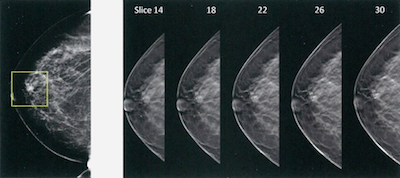

¿Sabes qué es un mamograma digital 3D?

El mamograma digital 3D, es una excelente herramienta en la detección temprana del cáncer de mama. El objetivo de la mamografía es detectar tumores en su etapa más temprana y más tratable. La tasa de supervivencia a 5 años del cáncer de mama con detección temprana es del 100%. Este sistema detecta tumores que sonContinue reading “¿Sabes qué es un mamograma digital 3D?”